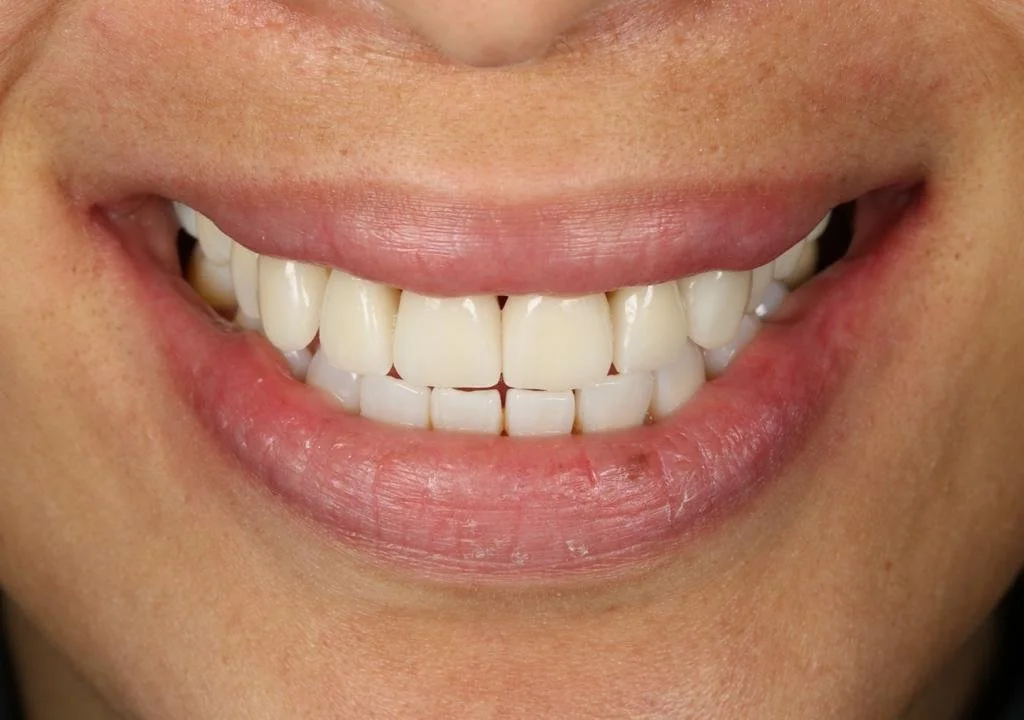

Cerec Reshape and Stain Graze